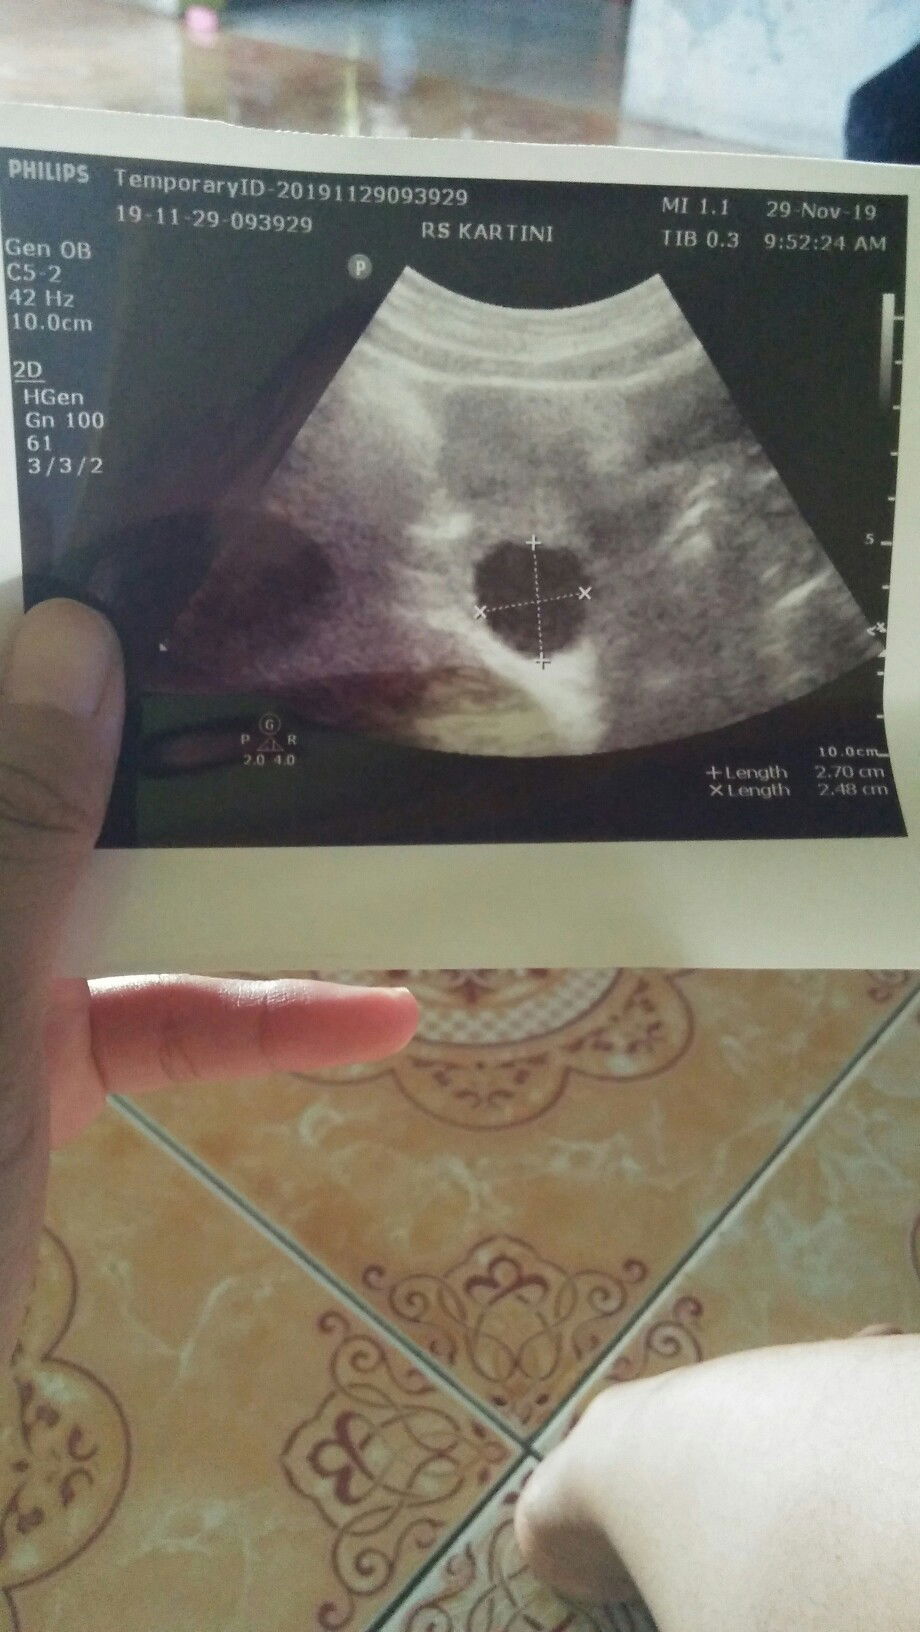

Bund ada gak hasil usgnya yg kayak gini,ini kata dokter ada kista di dalam perut saya,kemungkinan saya hamil di luar kandungan,apakah ada hasil usg yg kayak gini,mohon jawabannya ya bund?